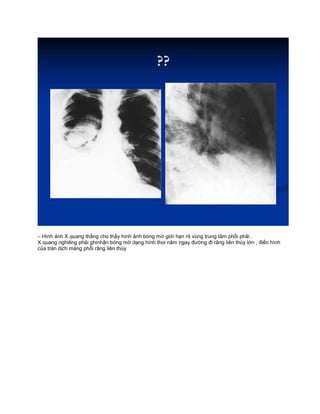

– Hình ảnh X quang thẳng cho thấy hình ảnh bóng mờ giới hạn rõ vùng trung tâm phổi phải .

X quang nghiêng phải ghinhận bóng mờ dạng hình thoi năm ngay đường đi rãng liên thùy lớn , điển hình

của tràn dịch màng phổi rãng liên thùy

– Hình ảnhX quang thẳng cho thấy hình ảnh bóng mờ giới hạn rõ vùng trung tâm phổi phải . X quang nghiêng phải ghinhận bóng mờ dạng hình thoi năm ngay đường đi rãng liên thùy lớn , điển hình của tràn dịch màng phổi rãng liên thùy